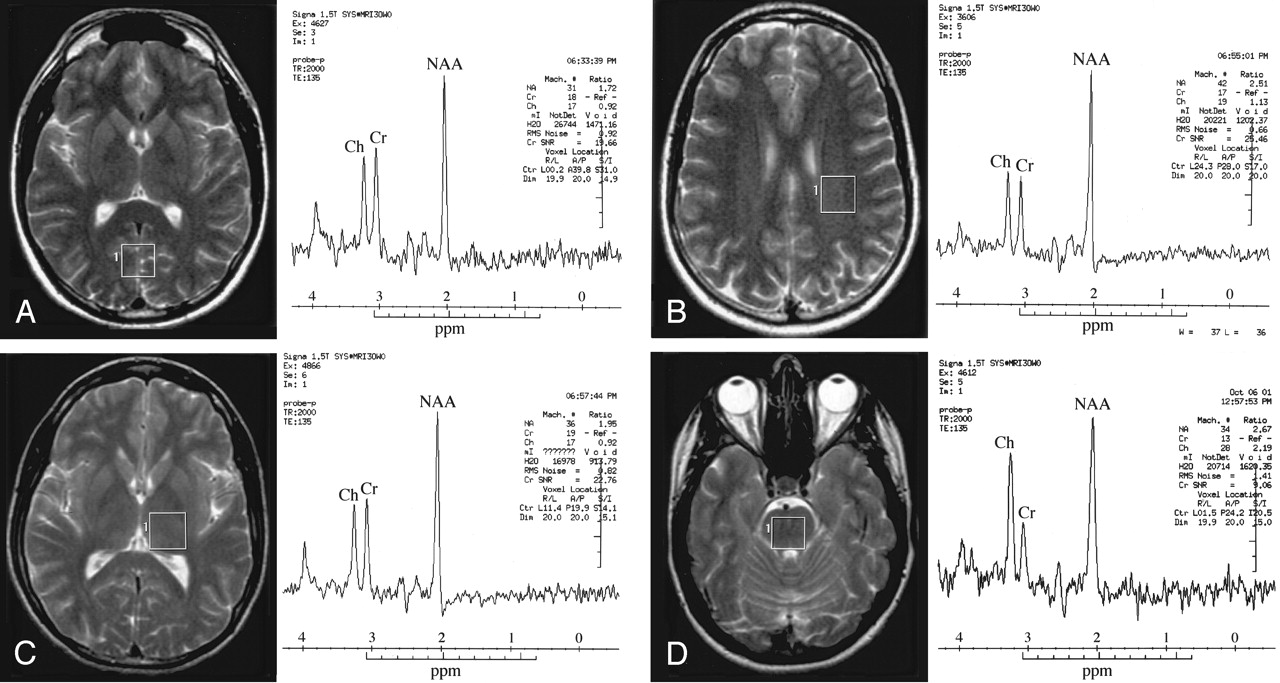

In the examination time available, each of the 10 brain regions could not be studied in each subject, so spectra from three or four regions were sampled in three different subject groups. In group 1, spectra were collected from three brain regions of 22 subjects (10 men and 12 women): the occipital lobe gray matter, which included aspects of the cuneus, lingual gyrus and calcarine fissure; the lentiform nuclei (basal ganglia); and the posterior white matter (primarily the subcortical white matter in the parietal lobe). In group 2, spectra were collected from the frontal gray matter (superior frontal gyri), frontal white matter (subcortical white matter bordering superior and middle frontal gyri), and pons of 31 subjects (12 men and 19 women). Spectra were also collected from the temporal gray matter (primary auditory cortex in posterior aspect of the superior temporal gyrus) of 15 group 2 subjects. In group 3, spectra were collected from the thalamus, cerebellar hemisphere, and parietal gray matter (middle aspect of the intraparietal sulcus) of 20 subjects (10 men and 10 women). As in group 2, spectra were also collected from the temporal gray matter of 13 group 3 subjects. Figure 1 illustrates the four different brain regions and their corresponding spectra.

Single voxel PRESS proton MR spectra (TR/TE = 2000/135) demonstrate choline (Ch), creatine (Cr), and N-acetylaspartate (NAA) peaks from occipital gray matter (A), posterior white matter (B), thalamus (C), and pons (D). The axial T2 FSE image shows the voxel location for the acquired spectrum. The chemical shift scale is in parts per million relative to tetramethylsilane.

The omnibus MANOVA for the NAA/Cr ratio collapsed across the three groups and 10 brain regions revealed a main effect of brain region (F[9, 213] = 27; P < .0001), which indicates regional variation for the NAA/Cr ratio. There was no main effect of sex (F[1, 213] = 0.123; P = .73) and no interaction between brain region and sex (F[9, 213] = 0.614; P = .78). Table 1 lists the mean NAA/Cr ratio and standard deviation (SD) for the 10 brain regions, collapsed across sex. The omnibus MANOVA for the Ch/Cr ratio demonstrated a main effect of brain region (F[9, 213] = 85; P < .0001), which again indicates regional variation of Ch/Cr. There was no effect of sex (F[1, 213] = 1.26; P = .26) and no interaction between brain region and sex (F[9, 213] = 0.742; P = .67). Table 2 shows the mean Ch/Cr ratio and SD for the 10 brain regions, collapsed across sex. Figure 1 illustrates the MR spectra obtained from different brain regions.